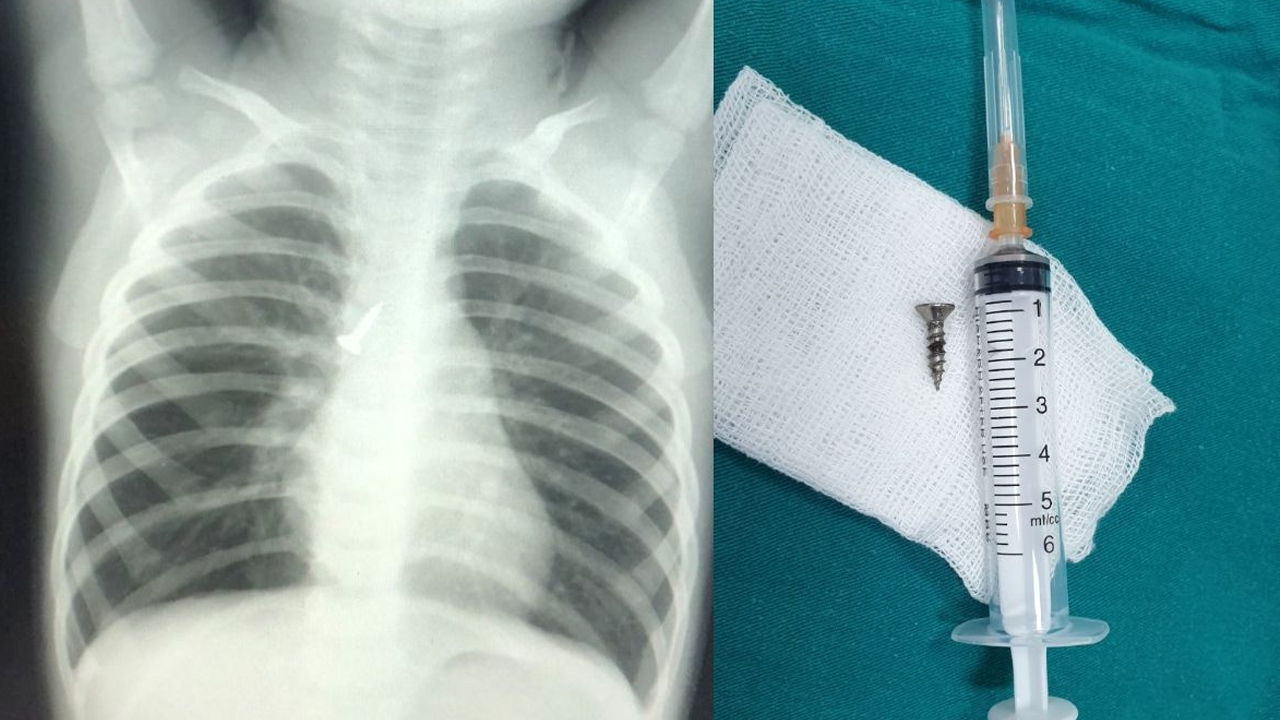

• Các bác sĩ Bệnh viện trẻ em Hải Phòng vừa gắp thành công đinh vít bằng kim loại dài 1,5 cm găm vào phế quản, cứu sống bé trai 22 tháng tuổi.

Sáng 13.8, bác sĩ (BS) Bùi Văn Chiến, Giám đốc Bệnh viện trẻ em Hải Phòng, cho biết bệnh viện vừa cấp cứu thành công một bé trai 22 tháng tuổi bị đinh vít găm vào phế quản.

Kết quả chụp X-quang cho thấy dị vật là một đinh vít bằng kim loại dài 1,5 cm đang ở phế quản gốc bên phải, đầu nhọn hướng lên trên.

Cấp cứu kịp thời bé 22 tháng tuổi bị đinh vít găm vào phế quản - ảnh 1

Xác định đây là ca bệnh khó, nguy cơ tai biến thủng đường thở hay rách đường thở do đầu nhọn ốc vít di chuyển gây ra, BS Đoàn hội chẩn cùng BS Vũ Trọng Tài - người trực tiếp làm thủ thuật cho bé đã cân nhắc lựa chọn phương pháp lấy dị vật. Trong thời gian 5 phút, BS Tài sử dụng ống nội soi mềm đã gắp thành công chiếc đinh ốc vít sắc nhọn mà không gây thương tổn cho đường thở. Hiện sức khỏe bé T. đang hồi phục ổn định.

Thông tin với Thanh Niên, BS Tài cho biết đây là trường hợp may mắn. Cháu bé không phải can thiệp bằng biện pháp phẫu thuật do dị vật chưa cắm thủng phế quản.